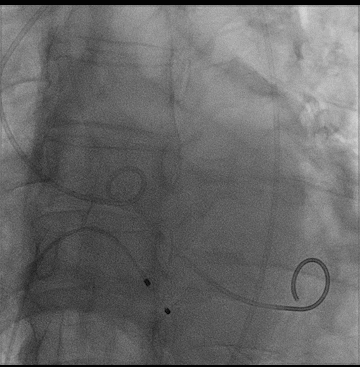

右股动脉入路、植入30型号瓣膜,

监护麻醉,经右侧股动脉行极简式TAVR,临时起搏器起搏,植入VitaFlow30瓣膜

主动脉根部造影